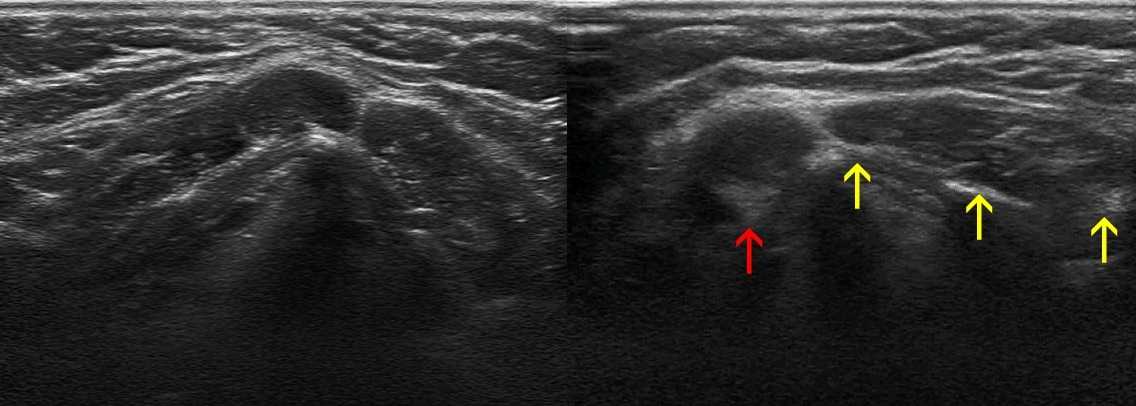

Рисунок. На УЗИ гипоэхогенные округлые образования похожие на лимфоузлы (1). Датчик развернули на 90°, слева видно гипоэхогенный овальный лимфоузел (красная стрелка), а в справа — продольный срез мышы (желтые стрелки).

Рисунок. На УЗИ видно гипоэхогенный лимфоузел в окружении трех анэхогенных сосудов. Режим ЦДК подтверждает нашу догадку.